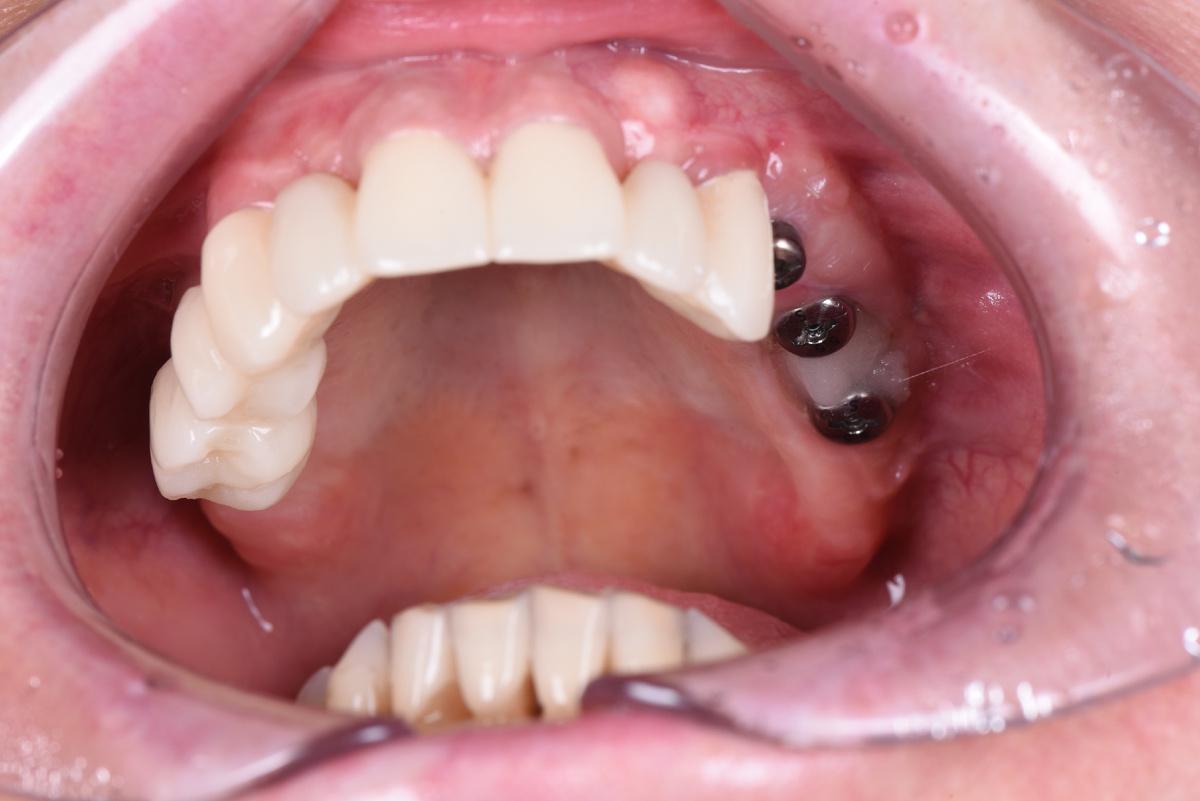

И, наконец, последний хирургический этап — установка 2 имплантатов в 3-ем сегменте слева. В данной области, где дефицит кости был самым катастрофическим, остеоинтеграция заняла 12 месяцев ️ Результат через месяц после установки формирователей и процедуры обязательного восстановления мягких тканей:

Протезирование

Оставим за скобками мероприятия по изготовлению временных конструкций, служивших не более, чем небольшим утешением нашей героине. Основная работа началась после имплантация зубов верхней челюсти, по традиции, с моделирования будущей улыбки на экране монитора (DSD)

Первая примерка :

Верхняя челюсть: 2 мостовидных протеза в жевательных отделах с опорой на 3 имплантата и мост на 6 единиц с опорой на 4 собственных зуба

Следующий шаг — коронки на нижние зубы:

Завершающий этап — после протезирования на имплантатах на нижней челюсти слева, в той области, где костная ткань восстанавливалась дольше всего